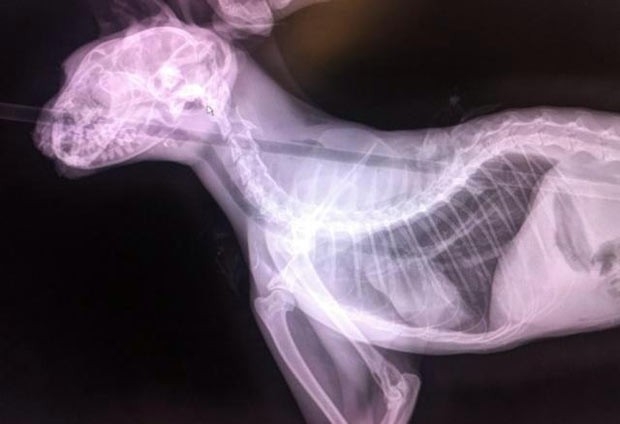

Raio-X mostra a flecha que atingiu o gato Quiver

A flecha entrou pela cabeça, atravessou o esôfago e saiu pelas omoplatas do animal, segundo funcionários da ONG One More Chance C.A.T.S.